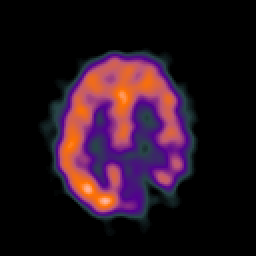

SPECT TC Study #6 -- Slice #37

[Home][Help][Clinical][Tour 1][Tour 2][Tour 3] Slice 37